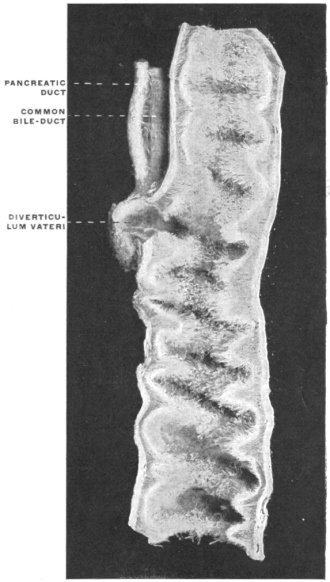

Fig. 8.—Blastodermic vesicle of mammal. (E. von Beneden.) The layer of cells lining the interior of the vesicle next to the zona pellucida forms Rauber’s “Deckschichte” or prochorion. This is not the true ectoderm, since it does not participate in the formation of the embryo, which is entirely derived from the cells of the germinal area.

Fig. 9.—Human embryo with yolk-sac, amnion, and belly-stalk of fifteen to eighteen days. (Heisler, after Coste.)

The remainder of the ovum, serving temporary purposes of nutrition and respiration, gradually becomes absorbed and disappears.

Fig. 10.—Embryonal area of sheep, composed of ectoderm and entoderm. (After Bonnet.)

Fig. 11.—Blastodermic vesicle of rabbit. Section through embryonic area at caudal limit of node of Hensen. (Rabl.)

Transverse sections at right angles to the long axis of the embryonic area show that the single layer of cells composing the primitive germinal membrane becomes differentiated first into two (Fig. 10) and subsequently into three layers of cells (Fig. 11). At the margins of the germinal area these layers are of course continuous with the rest of yolk-sac wall. From their position in reference to the center of the cell the three layers of the blastoderm are described as—

1. The outer, Epiblast or Ectoderm.

2. The middle, Mesoblast or Mesoderm.

3. The inner, Hypoblast or Entoderm.